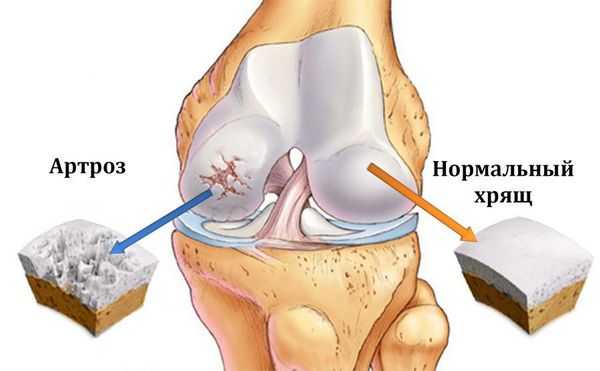

Остеоартроз (артроз) — заболевание суставов, характеризующееся дегенеративным изменением покрывающего кость хряща, проще говоря, его разрушением.

Патогенез остеоартроза

Основной питательной средой сустава является синовиальная жидкость. Она же выполняет и роль смазывающего агента между суставными поверхностями. Огромную и главную роль в развитии остеоартроза отводят метаболическим процессам в суставе и в его структурах. На начальной стадии, когда развиваются биохимические нарушения в синовиальной жидкости, ее свойства снижаются, что запускает механизм разрушения. Первой под удар попадает синовиальная оболочка сустава, которая выполняет важную роль мембраны и является подобием фильтра для самого главного питательного вещества хряща — гиалуроновой кислоты, не давая ей покинуть ее основное место работы — полость сустава. Насыщенность свойств суставной жидкости определяет ее циркуляция, чего без регулярного движения самого сустава быть не может. Отсюда и известная фраза «движение — это жизнь». Постоянная циркуляция синовиальной жидкости в полости сустава — залог полноценного обмена веществ в нем. При недостатке питательных веществ хрящ истончается, образование новых клеток останавливается, суставная поверхность становится неровной, грубой, с участками дефектов. Известна взаимосвязь между заболеваниями вен нижних конечностей (например, варикоз) и развитием нарушений обмена веществ в суставах, преимущественно коленных. [6] Костная структура, находящаяся под хрящевой, отвечает на процесс компенсаторным механизмом — она утолщается, становится грубее и расширяет зону покрытия, в результате чего образуются экзостозы и остеофиты, что и является основной причиной ограничений и деформаций сустава. Синовиальная жидкость насыщается клетками воспаления и элементами распада, суставная капсула в ответ на это утолщается, становится грубой и теряет эластичность, мягкие ткани буквально становятся сухими (происходит их дегидратация), отсюда и жалобы на утреннюю скованность, «стартовые боли». Патологический процесс в последних стадиях провоцирует организм включить последний компенсаторный механизм — обездвиживание. В состоянии покоя и так называемом физиологическом положении болезненность минимальна, связочный аппарат максимально расправлен. В таком положении сустав стремится зафиксироваться, и ему это удается быстрым образованием более грубых экзостозов, которые «фиксируют» сустав, а пациент при этом теряет способность полноценно двигать им. Мышцы такой конечности гипотрофируются, становятся слабее и меньше. Такие изменения уже считаются необратимыми.